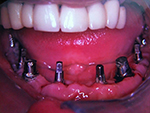

Komplett-Implantation: